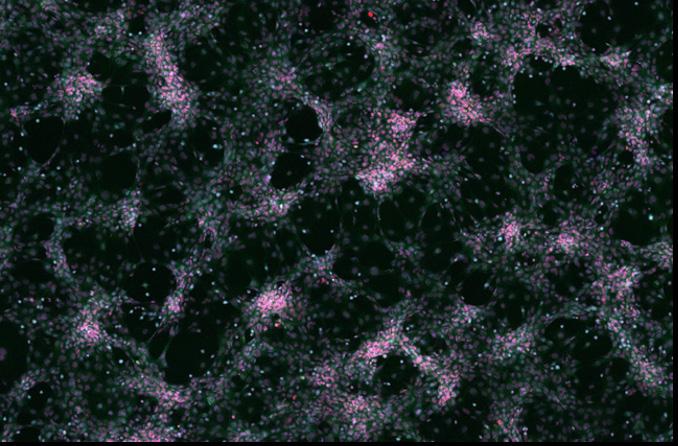

Images of the TAMs in the optimized conditions were acquired using a fluorescent light microscope (Figure 4). Significantly more CD206 expression, appearing in magenta (Cy5), can be observed in the HCC1954 condition compared to the negative control and the BT474 condition. Appearing in cyan (DAPI) are cell nuclei.

Figure 4: Images of TAMs taken on a Cytell® microscope at a 10x magnification. A significant increase in CD206 marker intensity (Cy5) is shown after exposure to HCC1954 CM, matching quantitative data from Figure 3.4.